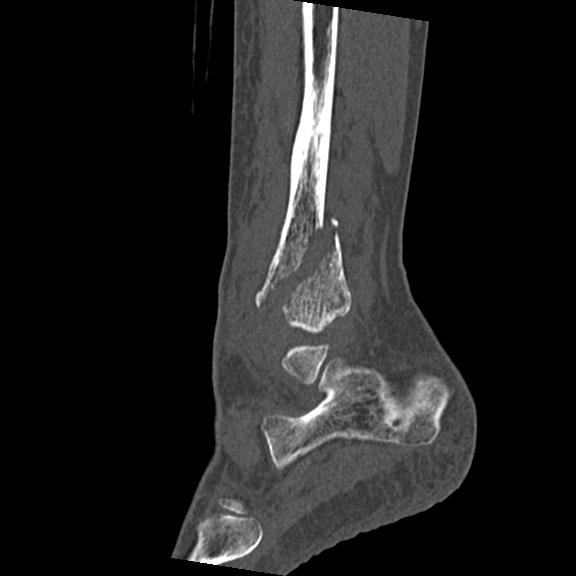

56476 8/28 4R 1/21 2R 左足関節 デジカメ写真 72歳女性 右足関節AS